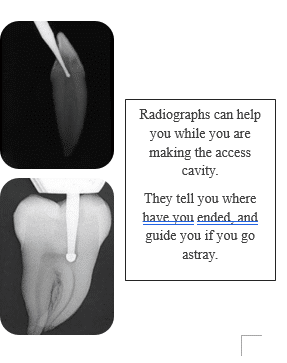

Take radiographs to guide preparation and verify position.

Protocol: Use a preoperative radiograph for anatomy and an immediate post-access radiograph to check depth and location relative to orifices.